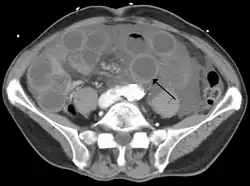

Computed tomography (CT) showing dilated loops of small bowel with thickened walls (black arrow), findings characteristic of ischemic bowel due to thrombosis of the superior mesenteric vein. | |